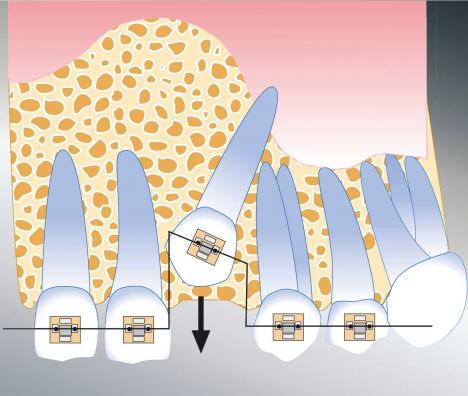

Kommt es nicht zum regelrechten Durchbruch bleibender Zähne, muss dem Durchbruch chirurgisch nachgeholfen werden. Der Zahn wird chirurgisch freigelegt und ein kleiner Metallknopf angeklebt. Über diesen Knopf zieht der Kieferorthopäde den Zahn in seine reguläre Position.

Kommt es zum frühzeitigen Verlust eines Backenzahnes oder ist ein Zahn nicht angelegt, ist im jugendlichen Alter ein Lückenschluss sinnvoll. Durch das Einbringen von temporären Miniimplantaten kann die Behandlung nicht nur beschleunigt, sondern auch deutlich exakter durchgeführt werden.